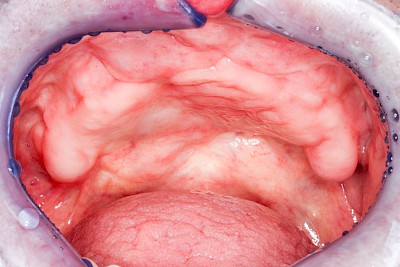

In seltenen Fällen schwindet nur der Knochen, aber nicht die bedeckenden Schleimhäute. In diesen Fällen spricht man von einem sogenannten "Schlotterkamm".